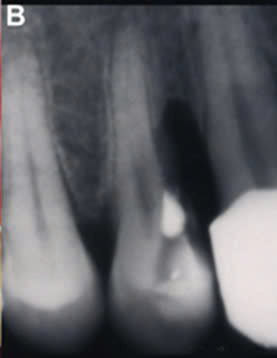

Hình 5: Hình ảnh thiếu hổng xương sau khi phẫu thuật xương bị hoại tử do sử dụng arsenic trong điều trị nội nha răng 25 8.

Việc phẫu thuật cắt bỏ xương và răng bị hoại tử để lại thiếu hổng xương lớn gây khó khăn trong phục hồi lại răng mất cho bệnh nhân sau này. Đặt arsenic trong buồng tủy quá 3 ngày có thể gây các tác động xấu lên răng, xương ổ răng và lợi9